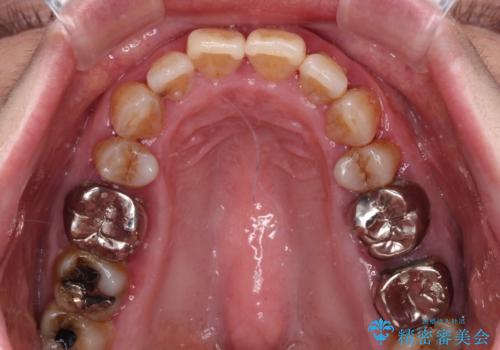

- インプラント治療を前提に下顎の部分矯正を始めたものの、そのまま長い間放置しているとのことで来院された患者様です。

全体的に歯肉が腫れており、歯周病により抜歯をしなければならない歯がある状態でした。

治療前は磨き残しが多く見られ、全体的に歯肉が腫れている状態でしたが、抜歯の必要な歯を抜いたことで口腔内の環境が改善され、磨き残しも少なくなってきました。